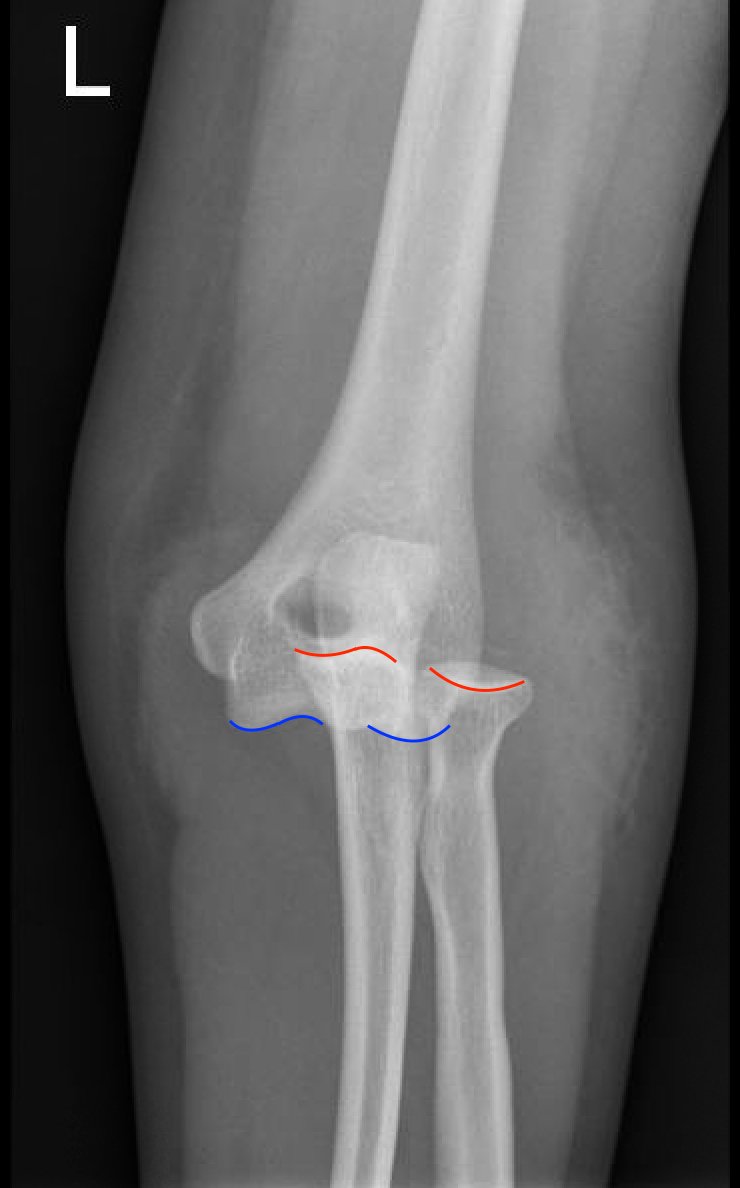

Posterior Elbow Dislocation, AP XRay, dislocated, Annotated. JETem 2016

Posterior Elbow Dislocation